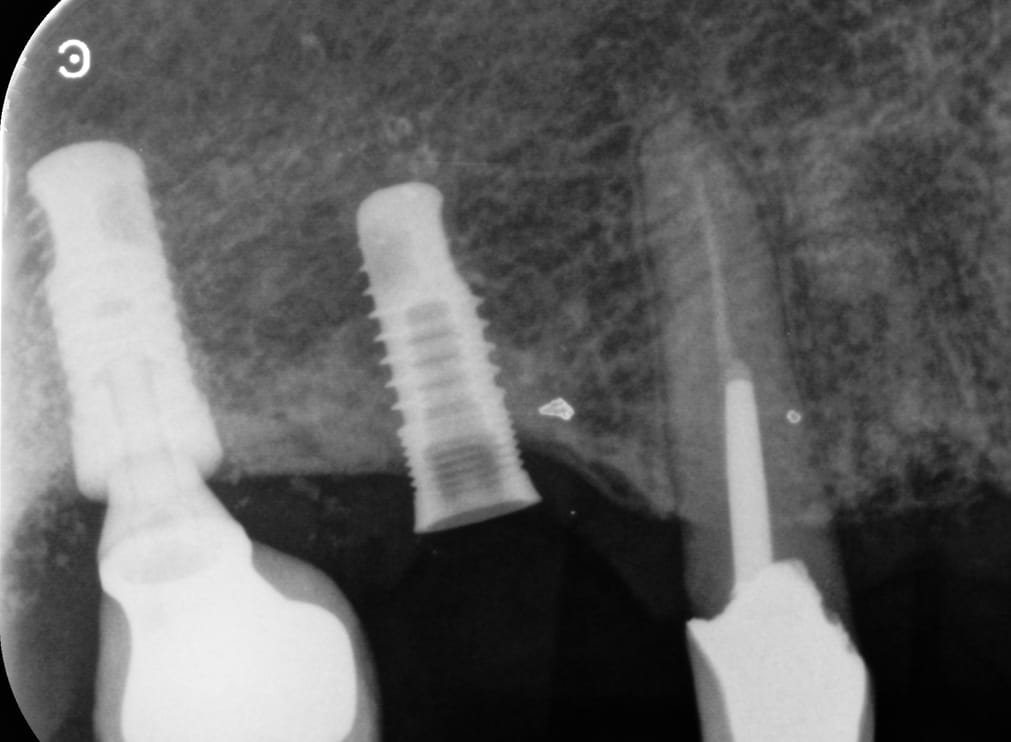

Nous aimerions connaitre la marque de cet implant.

SERF ( GlobalD maintenant) EVL N

https://www.spotimplant.com/fr/implants-dentaire/serf-implanter-innovation/evl-n